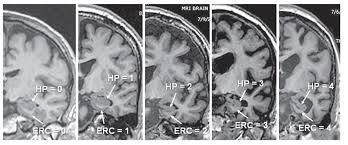

Lewy, the scientist who discovered them. Loss of substantia nigra hyperintensity on 7 tesla mri of parkinson's disease, multiple system atrophy, and progressive supranuclear palsy. Besides nuclear imaging methods, the clinical utility of structural neuroimaging with magnetic resonance imaging (mri) for differential comparison between dementia with lewy bodies and alzheimer's disease. You also might see things that aren't there, called hallucinations. Lbd is a term that covers two conditions that have similar. Protein deposits, called lewy bodies, develop in nerve cells in the brain regions involved in thinking, memory and movement (motor control). Certain nuclear scans of the brain, including positron emission. How is lewy body dementia (ldb) diagnosed? Dr michael firbank discusses his study using functional mri in lewy body dementia and alzheimer's disease at the newcastle university institute. Focal atrophy in dementia with lewy bodies on mri: Memory loss is not always an early symptom. Lewy body dementia (lbd) is a type of progressive dementia. Many people also experience changes in alertness including daytime sleepiness, confusion or staring spells.

The lewy body society (see end of leaflet) is a registered uk charity which has a website full of information. Dementia with lewy bodies or lewy body dementia is dementia caused by the presence of lewy bodies in the brain. Loss of substantia nigra hyperintensity on 7 tesla mri of parkinson's disease, multiple system atrophy, and progressive supranuclear palsy. Also, there is a helpline for support provided by dementia. It is reported as the second most common form of dementia following alzheimer diseas.